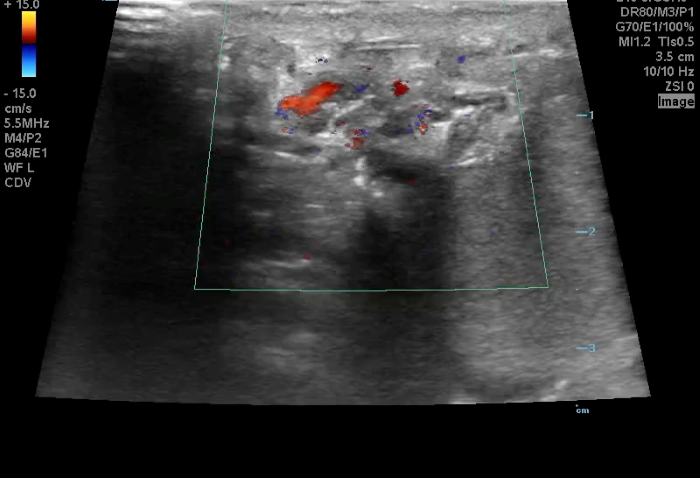

Torsion - Image 1_crop.pngImage 1. Color Doppler of a testicle without blood flow to the body of the testicle concerning for testicular torsion.

In your first image (Image 1), you realize there is no flow with color Doppler. Additionally, you find a torsed cord complex (Image 2), also known as the “corkscrew sign.” You consult Urology who is busy in the operating room with another case. You decide to perform a manual detorsion due to your concern for testicular atrophy and risk of infertility. Using the open book technique, you get relief of pain and return of vertical positioning of the testicle after two rotations. On your repeat testicular POCUS with color Doppler you obtain these images (Images 3 and 4), which demonstrate venous and arterial flow throughout the testicle. The cord is now untwisted and appears linear in orientation.

Torsion - image 3_crop.pngImage 3. Color Doppler demonstrating intratesticular flow toward and away from the probe.